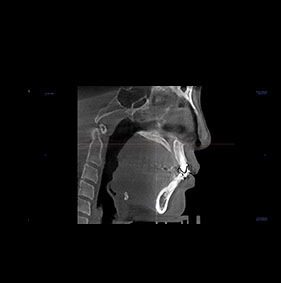

3D CT분석을 통한

정확한 코 재수술

원인 분석

코 재수술은 문제의 원인을

정확한 파악하는 것이 중요합니다.

V브이성형외과의

코성형 전담 의료진은

환자와 면밀한 상담을 통해서

현재 불만족의 원인을 파악하고

개선을 위한 방법을 모색합니다.

3D CT 분석을 통해서 해부학적인 상태를 확인하고,

기존 코수술로 인한 문제를 파악할 수 있습니다.